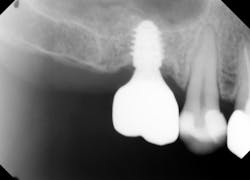

Therefore, if a patient has 5 mm of available bone height from the sinus floor, a maximum of 5 mm is prudent to expect from an indirect lift; therefore, an 8 mm to 10 mm implant is the ideal choice. The tapered iHex or MorsTorq implant provides safety when dealing with sinus areas, for three reasons. First, the taper helps prevent overinsertion toward the sinus cavity. Second, the abutment and transfer attached to the implant allows for more control. Finally, the rounded apex helps reflect the sinus floor without creating damage (figures 1-6).

Admittedly, there is some technique sensitivity in relation to both the open sinus and closed sinus lift procedures. A recent article about tapered implants placed in maxillary sites with residual bone height of 1 mm to 6 mm reported high success rates using a closed technique without grafting material, which led to bone formation beyond the original limit of the sinus floor.2